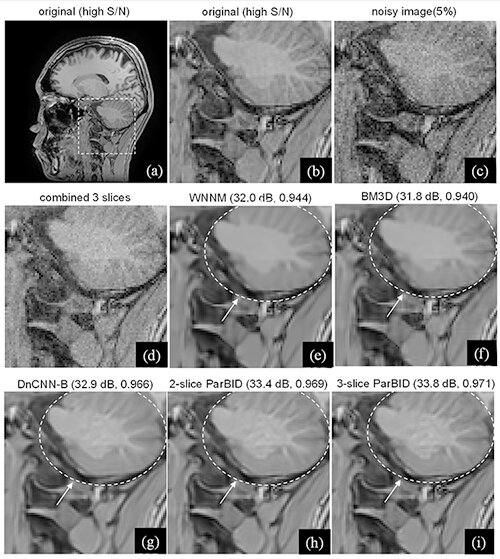

深層学習を利用した雑音除去法は、従来の非線形フィルタを大幅に上回る特性を示し、大きな注目を集めている。宇都宮大学学術院 伊藤聡志教授は、本研究において、MRI画像を対象とし、3つの観点から性能改善を図った。第1に活性化関数に従来のReLUではなくSwishを応用したこと、第2に雑音量が未知であり、かつ、空間可変な雑音画像に適応しうるブラインド雑音除去を導入したことである。第3に隣接する画像を線形加算して複数の加算画像を作成し、加算画像に対しブラインド雑音除去を行い、その後に連立方程式を解く並列型雑音除去法の導入である。実験の結果、Swishの採用によりReLUを上回るPSNRが得られた。また、並列型雑音除去法の採用により画質劣化を抑制した雑音除去を行えることが示された。

Swishを活性化関数に使用することにより雑音除去性能を改善することができた。また、ネットワークは画像内で雑音量が変化する場合であってもブラインド雑音除去の効果により良好に雑音除去できることが示された。ブラインド雑音除去を並列型雑音処理法に適用した方法では、単一の画像をブラインド雑音除去するよりも、生体構造の保存性を改善できることが示された。特に3枚の画像を使用する3-slice ParBIDのときに最も大きな改善が見られた。